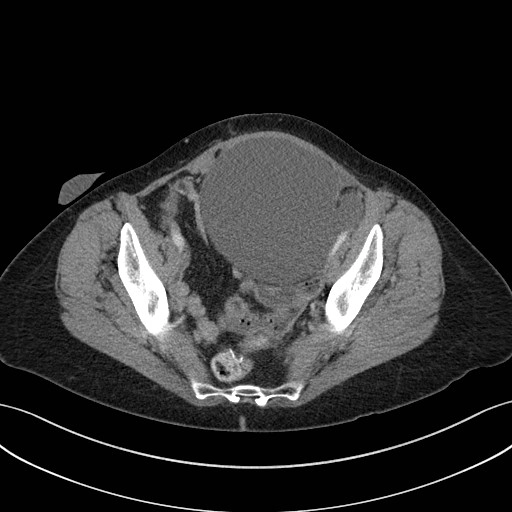

• Chấn thương thận

Chấn thương thận (Renal trauma)

Phân độ chấn thương thận AAST (AAST kidney injury scale)